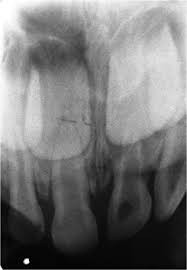

3. How old is the patient with the following X ray?